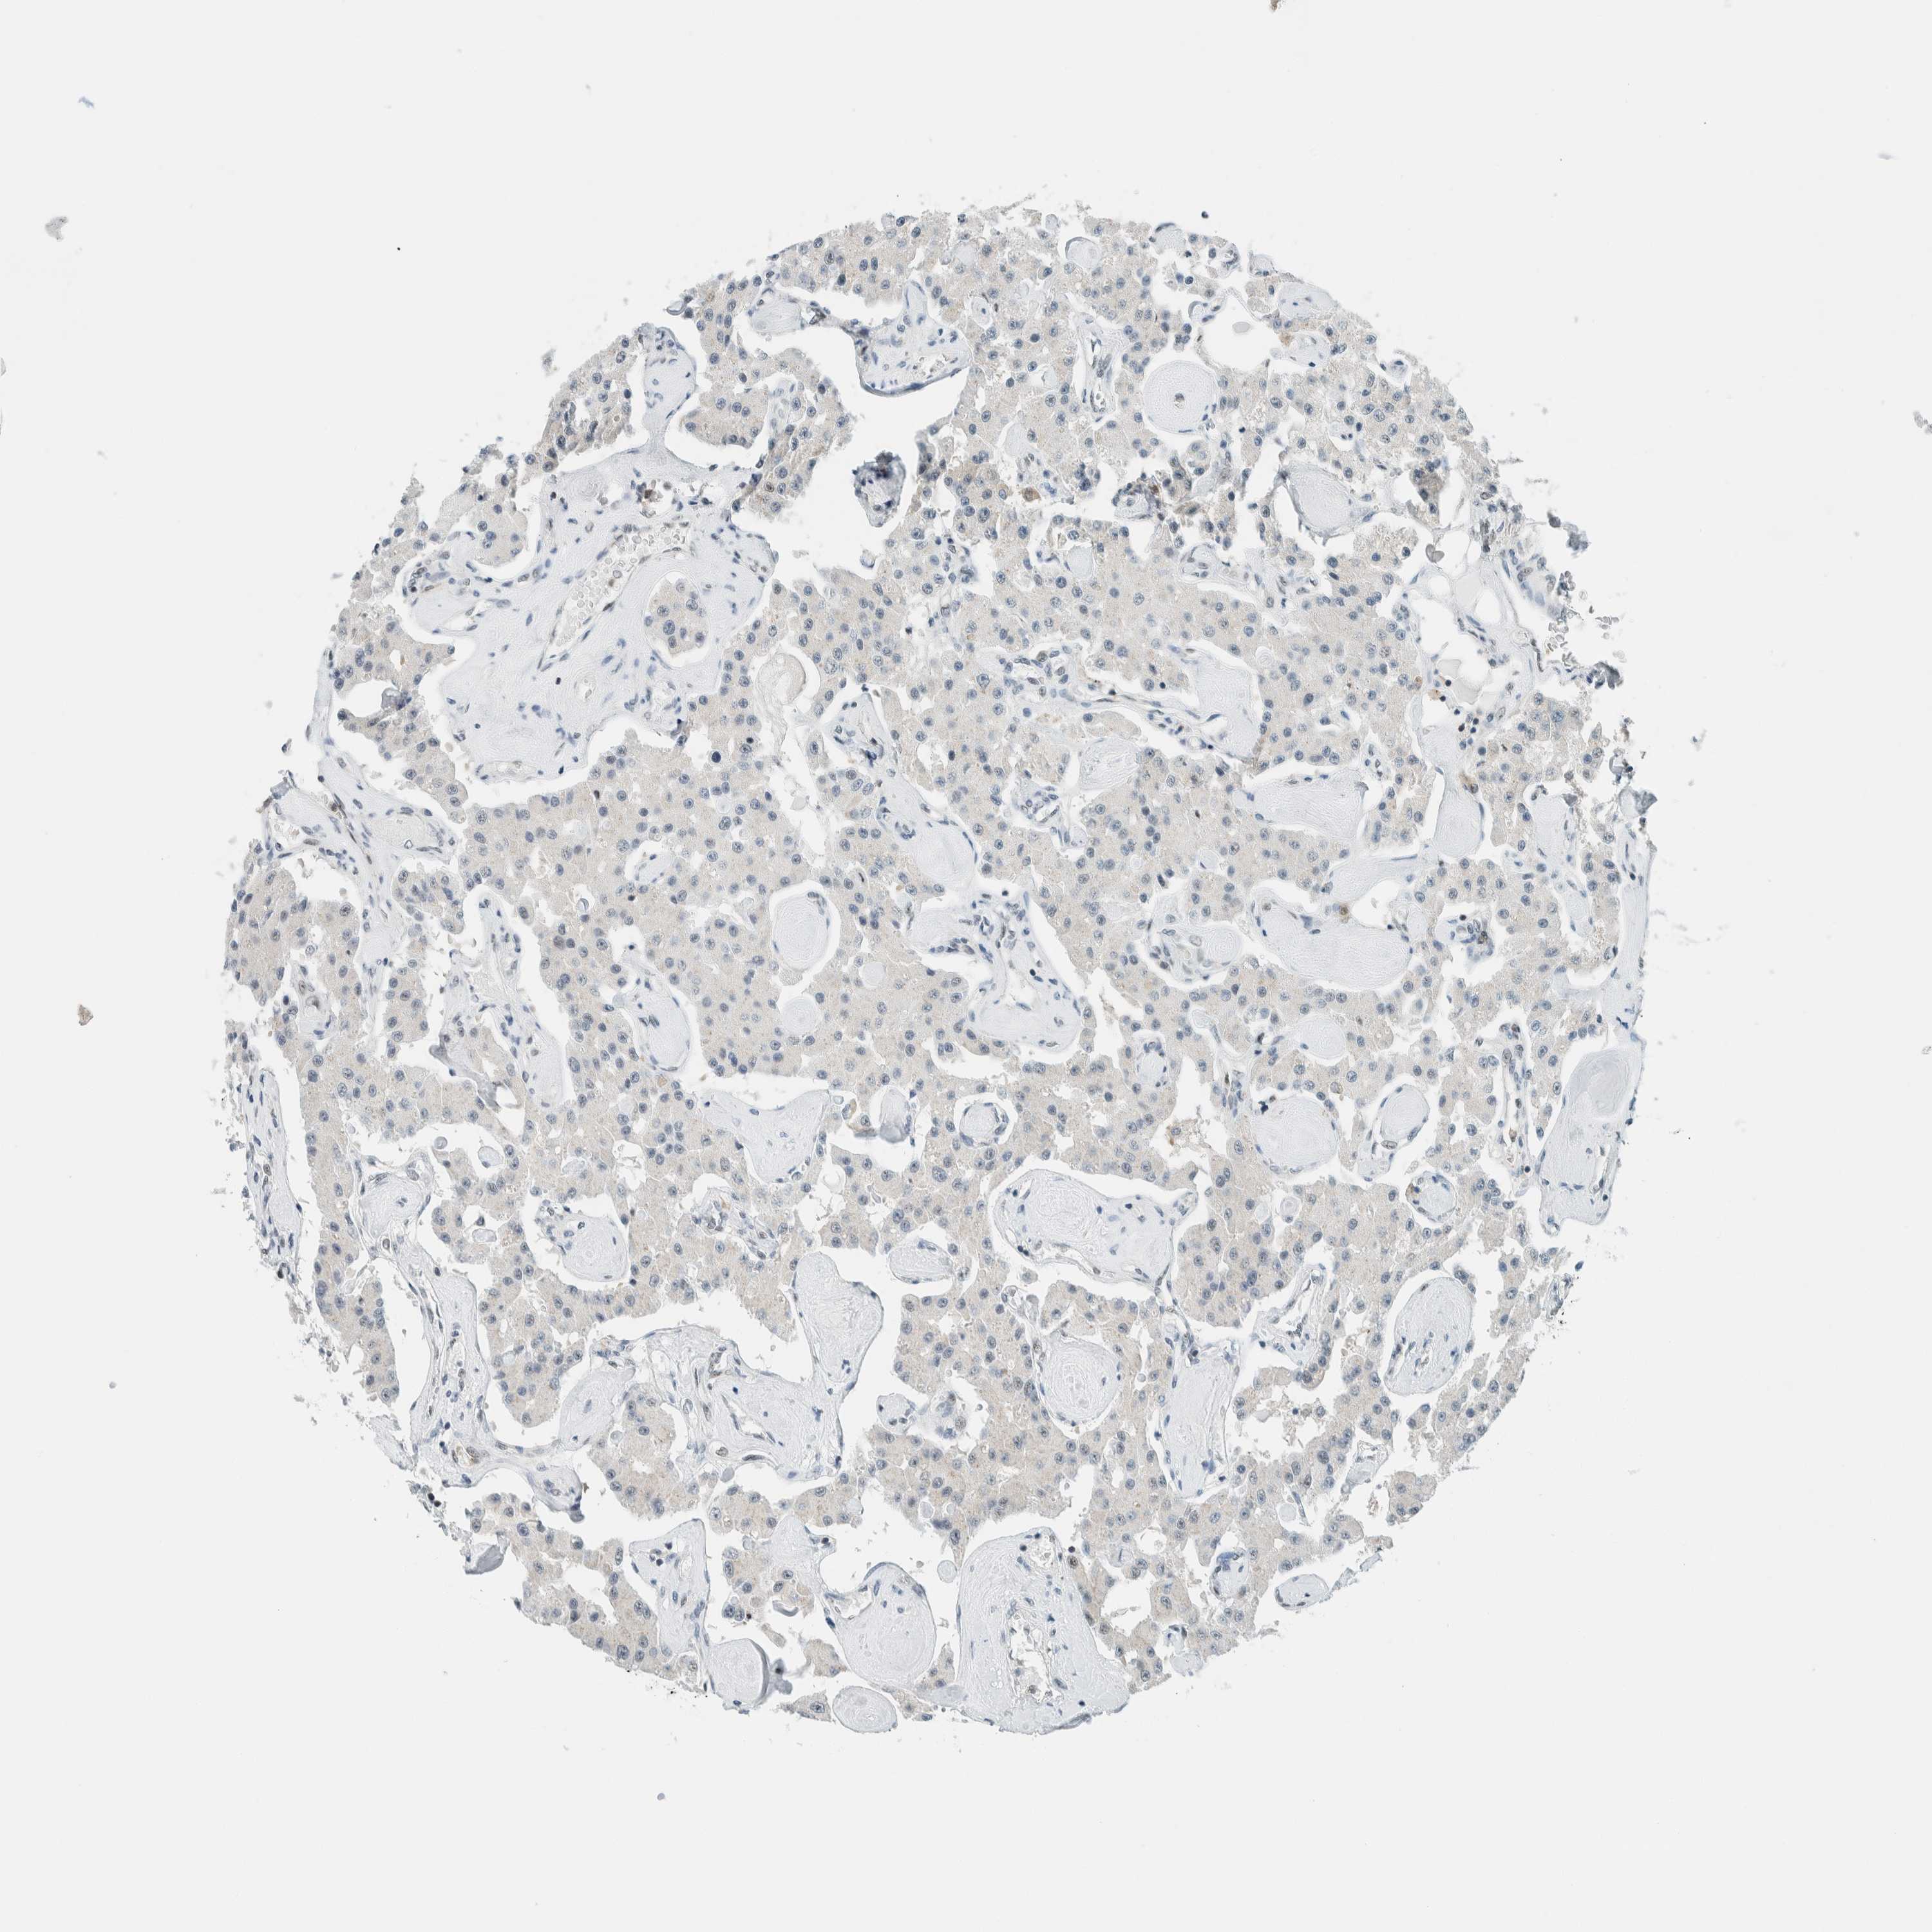

CARCINOID - Protein expressioni

A mouse-over function shows sample information and annotation data. Click on an image to view it in a full screen mode. Samples can be filtered based on level of antibody staining by selecting one or several of the following categories: high, medium, low and not detected. The assay and annotation is described here.

Each image is clickable and will lead to virtual microscopy that enables deeper exploration of all samples and also displays staining intensity scores, fraction scores and subcellular localization as well as patient and tissue information for each sample.

Antibody HPA021883

Antibody HPA021886

Staining

High

Medium

Low

Not detected

Intensity

Strong

Moderate

Weak

Negative

Quantity

>75%

75%-25%

<25%

None

Location

Nuclear

Cytoplasmic/membranous

Cytoplasmic/membranous,nuclear

Carcinoid, malignant, NOS

Carcinoma, NOS